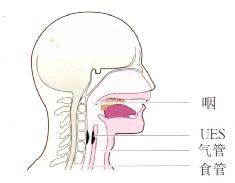

防止口腔内容物吸入气道主要依靠协调的吞咽反射,包括声门关闭及气道保护。防止反流的胃内容物吸入的机制包括上食管括约肌(UES)和反流物引起的食管蠕动(图3.19)。万一发生吸入,咳嗽和气管痉挛可保护肺。如果其中某些保护机制减弱则胃食管反流可引起肺部症状。

图3.19UES防止胃内容物反流。